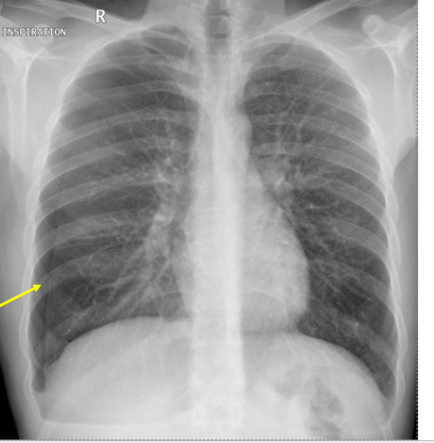

lung lesions - miliary TB 2. cardiomegaly 3. cavitations - pneumonia 4. hyperinflation COPD 5. pulmonary hypertension

**lung lesions - miliary TB** 2. cardiomegaly 3. cavitations - pneumonia 4. hyperinflation COPD 5. pulmonary hypertension